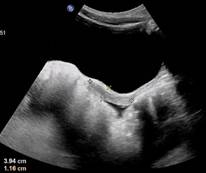

图1:青春发育前期子宫

图2:正常育龄期女性子宫

①女童超声检查指标:盆腔B超检测显示子宫长度大于3.2cm,卵巢容积 1-3 ml,并可见多个直径≥4 mm 的卵泡【1】。

②子宫内膜增厚,形态屈曲。

(2)性腺增大,即盆腔超声提示:女童子宫、卵巢容积增大且卵巢内可见多个直径≥4 mm 的卵泡,男童睾丸容积≥4 ml;